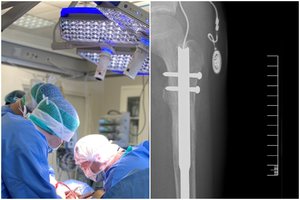

Buitinis kivirčas tarp pažįstamų jaunuolių baigėsi šūviu iš dujinio šautuvo, pritaikyto šaudyti šratais. Kulka pataikė į dešinį žandą. Išorėje – vos 0,5 cm dydžio skylutė, tačiau giliai audiniuose slėpėsi 5 mm dydžio metalinė dalelė.

Chirurgai ją pašalino per burnos ertmę, o vos po dviejų dienų pacientas jau išleistas namo. „Šis atvejis rodo, kad vadinamieji neletaliniai ginklai toli gražu nėra žaislai“, – pabrėžia medikai.